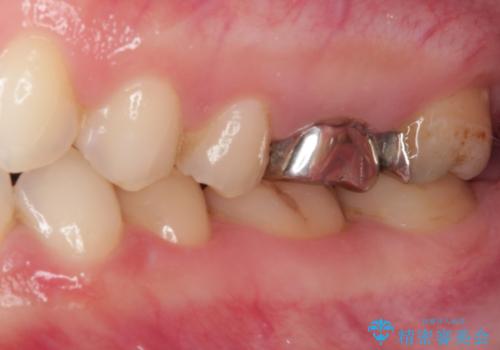

- 奥歯の銀歯をセラミックにしたいとのことで来院された患者様です。

当初は奥歯のみの治療をご希望でしたが、話を進めていくうちに、軽度ではあるものの、幼少期の薬の影響で歯が変色していることがコンプレックスであるということが分かりました。

長年歯の色が塞ぎ込んでいた部分があるとのことで、これを機会に全ての歯を真っ白にするために、オールセラミッククラウンにて補綴治療を行うこととしました。

より白さが目立つように、自然な仕上がりではなく、作り物の雰囲気があるフルジルコニアクラウンにて補綴治療を行いました。